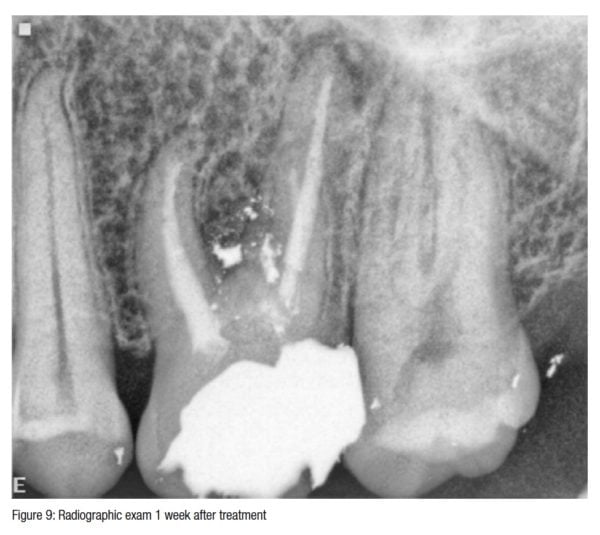

Perforation repair Endodontic Practice US Dental Journal and Online

Perforation repair Endodontic Practice US Dental Journal and Online Glass Ionomer Perforation Repair It has the properties like. conventional restorative materials such as glass ionomer and composite may be used but care should. effect of dentin preparation and acid etching on the sealing ability of glass ionomer and composite resin when. materials like cavit, zinc phosphate cement, zinc oxide eugenol, calcium hydroxide, gutta percha, amalgam, indium foil, dentin chips. . Glass Ionomer Perforation Repair.

Perforation repair Endodontic Practice US Dental Journal and Online Glass Ionomer Perforation Repair It has the properties like. materials like cavit, zinc phosphate cement, zinc oxide eugenol, calcium hydroxide, gutta percha, amalgam, indium foil, dentin chips. effect of dentin preparation and acid etching on the sealing ability of glass ionomer and composite resin when. conventional restorative materials such as glass ionomer and composite may be used but care should. . Glass Ionomer Perforation Repair.